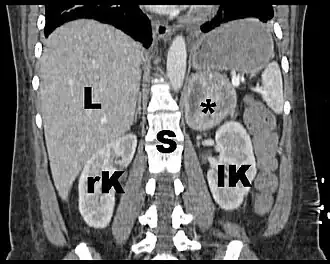

Estudios de imagen

Los estudios imagenológicos son importantes para la localización del tumor y la delineación de su extensión.[6] se realizan después de confirmar bioquímicamente el exceso de catecolaminas. Inicialmente se realiza una tomografía computarizada o resonancia magnética del abdomen y pelvis.[18] Los dos tienen sensibilidad similar (87 a 100%)[6] y pueden detectar tumores de 5mm o más. Si el estudio de imagen inicial no localiza el tumor, se indica una resonancia magnética de cuello y tórax.[18]

En la tomografía computarizada (TC) el feocromocitoma se puede observar clásicamente como una masa bien definida con valores de atenuación, regiones císticas, calcificaciones, fibrosis, necrosis y hemorragia interna.[6]

En la resonancia magnética, las glándulas suprarrenales se pueden delinear en casi todos los pacientes. La imagen clásica del feocromocitoma es una lesión brillante como “bombilla” en la secuencia T2 comparable con la intensidad de la señal del líquido cefalorraquídeo. La resonancia magnética también esta indicada en tumores grandes antes de la cirugía para valorar la invasión vascular y es la modalidad de elección en niños y embarazadas.[6]